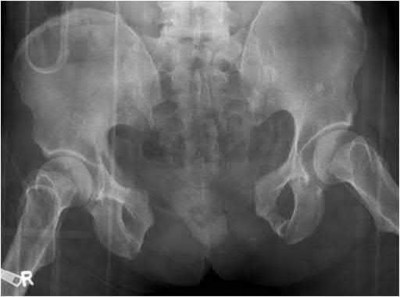

Question 11:

A poly-trauma patient presents hemodynamically unstable with an anteroposterior compression (APC-III) pelvic ring injury. A circumferential pelvic binder is requested to reduce pelvic volume and control hemorrhage. To be anatomically effective, the binder must be centered precisely over which of the following landmarks?

Correct Answer: Greater trochanters

Explanation:

For optimal mechanical advantage and effective reduction of an 'open book' pelvic fracture (APC type), a pelvic binder must be applied directly over the greater trochanters of the femurs. Applying it higher, such as over the iliac crests, is a common error that fails to adequately close the pelvic ring and can paradoxically open the true pelvis.